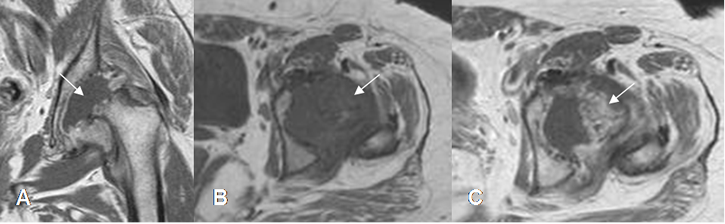

Fig 143 A. Artritis infecciosa.

A: RM coronal en T1. Destrucción de la cabeza femoral y derrame articular, por artritis infecciosa.

B: RM axial en T1 simple y C: RM axial en T1 con contraste. Proliferación sinovial, que realza con el contraste (Flechas).